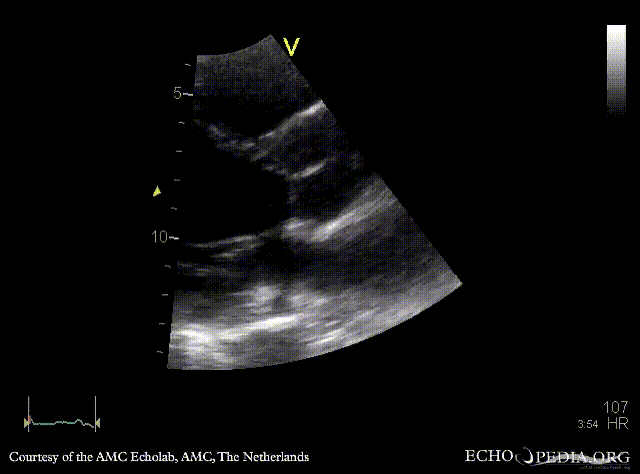

PLAX: no opening of aortic valve PLAX zoom